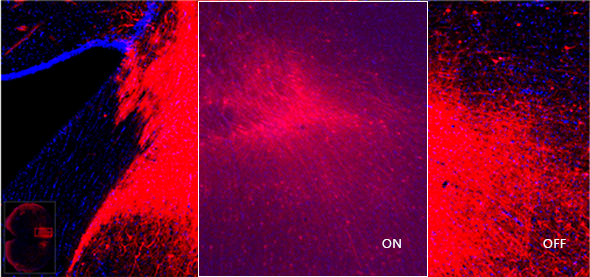

HDR(高动态范围)自动校正

全新的HDR(高动态范围)自动校正,实现了对样本图像进行动态对比度的全局调光,展示更多的HDR荧光信号的亮度细节,准确得到图像信息,避免发生在以往图像中较弱marker信号被忽略的现象,此外该功能的图像处理位深为16bit,呈现细腻的画面效果,为后续分析提供准确而相对完全的图像信息,拓宽使用者的科研思路,使样本承载更多分析价值。